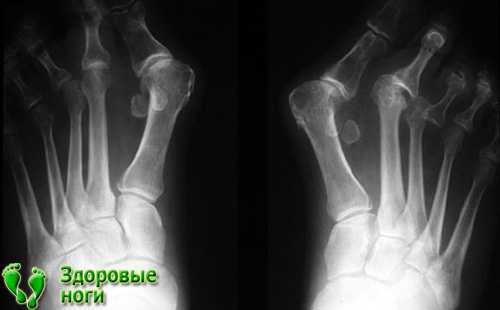

Как определить заболевание

Что делать, если появился твердый нарост? В первую очередь для того чтобы верно определить диагноз, необходимо посетить врача. Он произведет осмотр и установит предварительную стадию болезни. При осмотре доктор обращает внимание не только на изменения кости, но и на поверхность стопы, определяя ее чувствительность и функционирование. На приеме нужно подробно рассказать специалисту о том, как болит косточка на ноге около большого пальца, давности деформации и физических нагрузках.

После осмотра врач обязательно назначает дополнительные исследования, к которым можно отнести:

- рентгенографию нижних конечностей в трех проекциях;

- плантографию, в ходе которой устанавливает не только стадия болезни, но и уровень нагрузки на ноги;

- подометрию (определение давления на стопы).

Диагностика заболевания

Первый этап во время определения диагноза вальгусной деформации большого пальца – это зрительный осмотр врача и определение стадии болезни.Во время осмотра берутся во внимание, в каком состоянии подошвенные поверхности, упругость (тургор) верхней части ступни, а также сосудистый статус, определяется тактильная чувствительность стоп и функциональность фаланги.

Врач обязан рассмотреть все возможные ограничения передвижений стопы, чтобы точно определить причину патологии. С помощью расстояния между плюсневыми головками определяют степень деформации пальца.